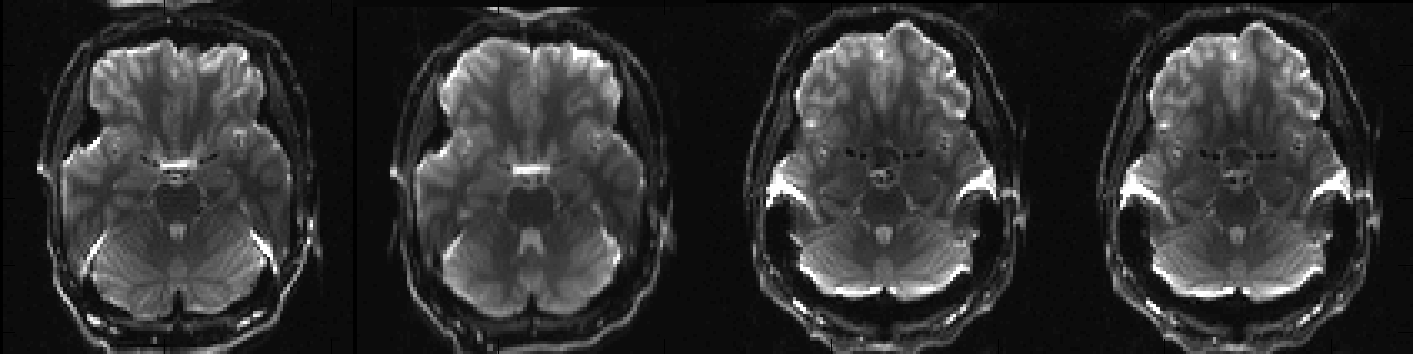

Above you can see a selected slice from the four volumes in an example file called my_b0_images.nii.gz. It is immediately obvious that the distortions in the first two images are vastly different from those in the two last images. If we take a look at the associated acqparams.txt file

we can see why. The two first images have been acquired with negative phase-encode blips in the y-direction, which means that signal from an area with "higher than expected" field (such as just above the ear-canals) will be displaced downwards. Conversely the two last images have been acquired with positive blips which means that signal from those same areas would be displaced upwards.

In addition to that we can see that the second image looks a little bit different to the first, despite having been acquired with identical parameters. This probably means that the subject moved between the acquisitions of the two images.